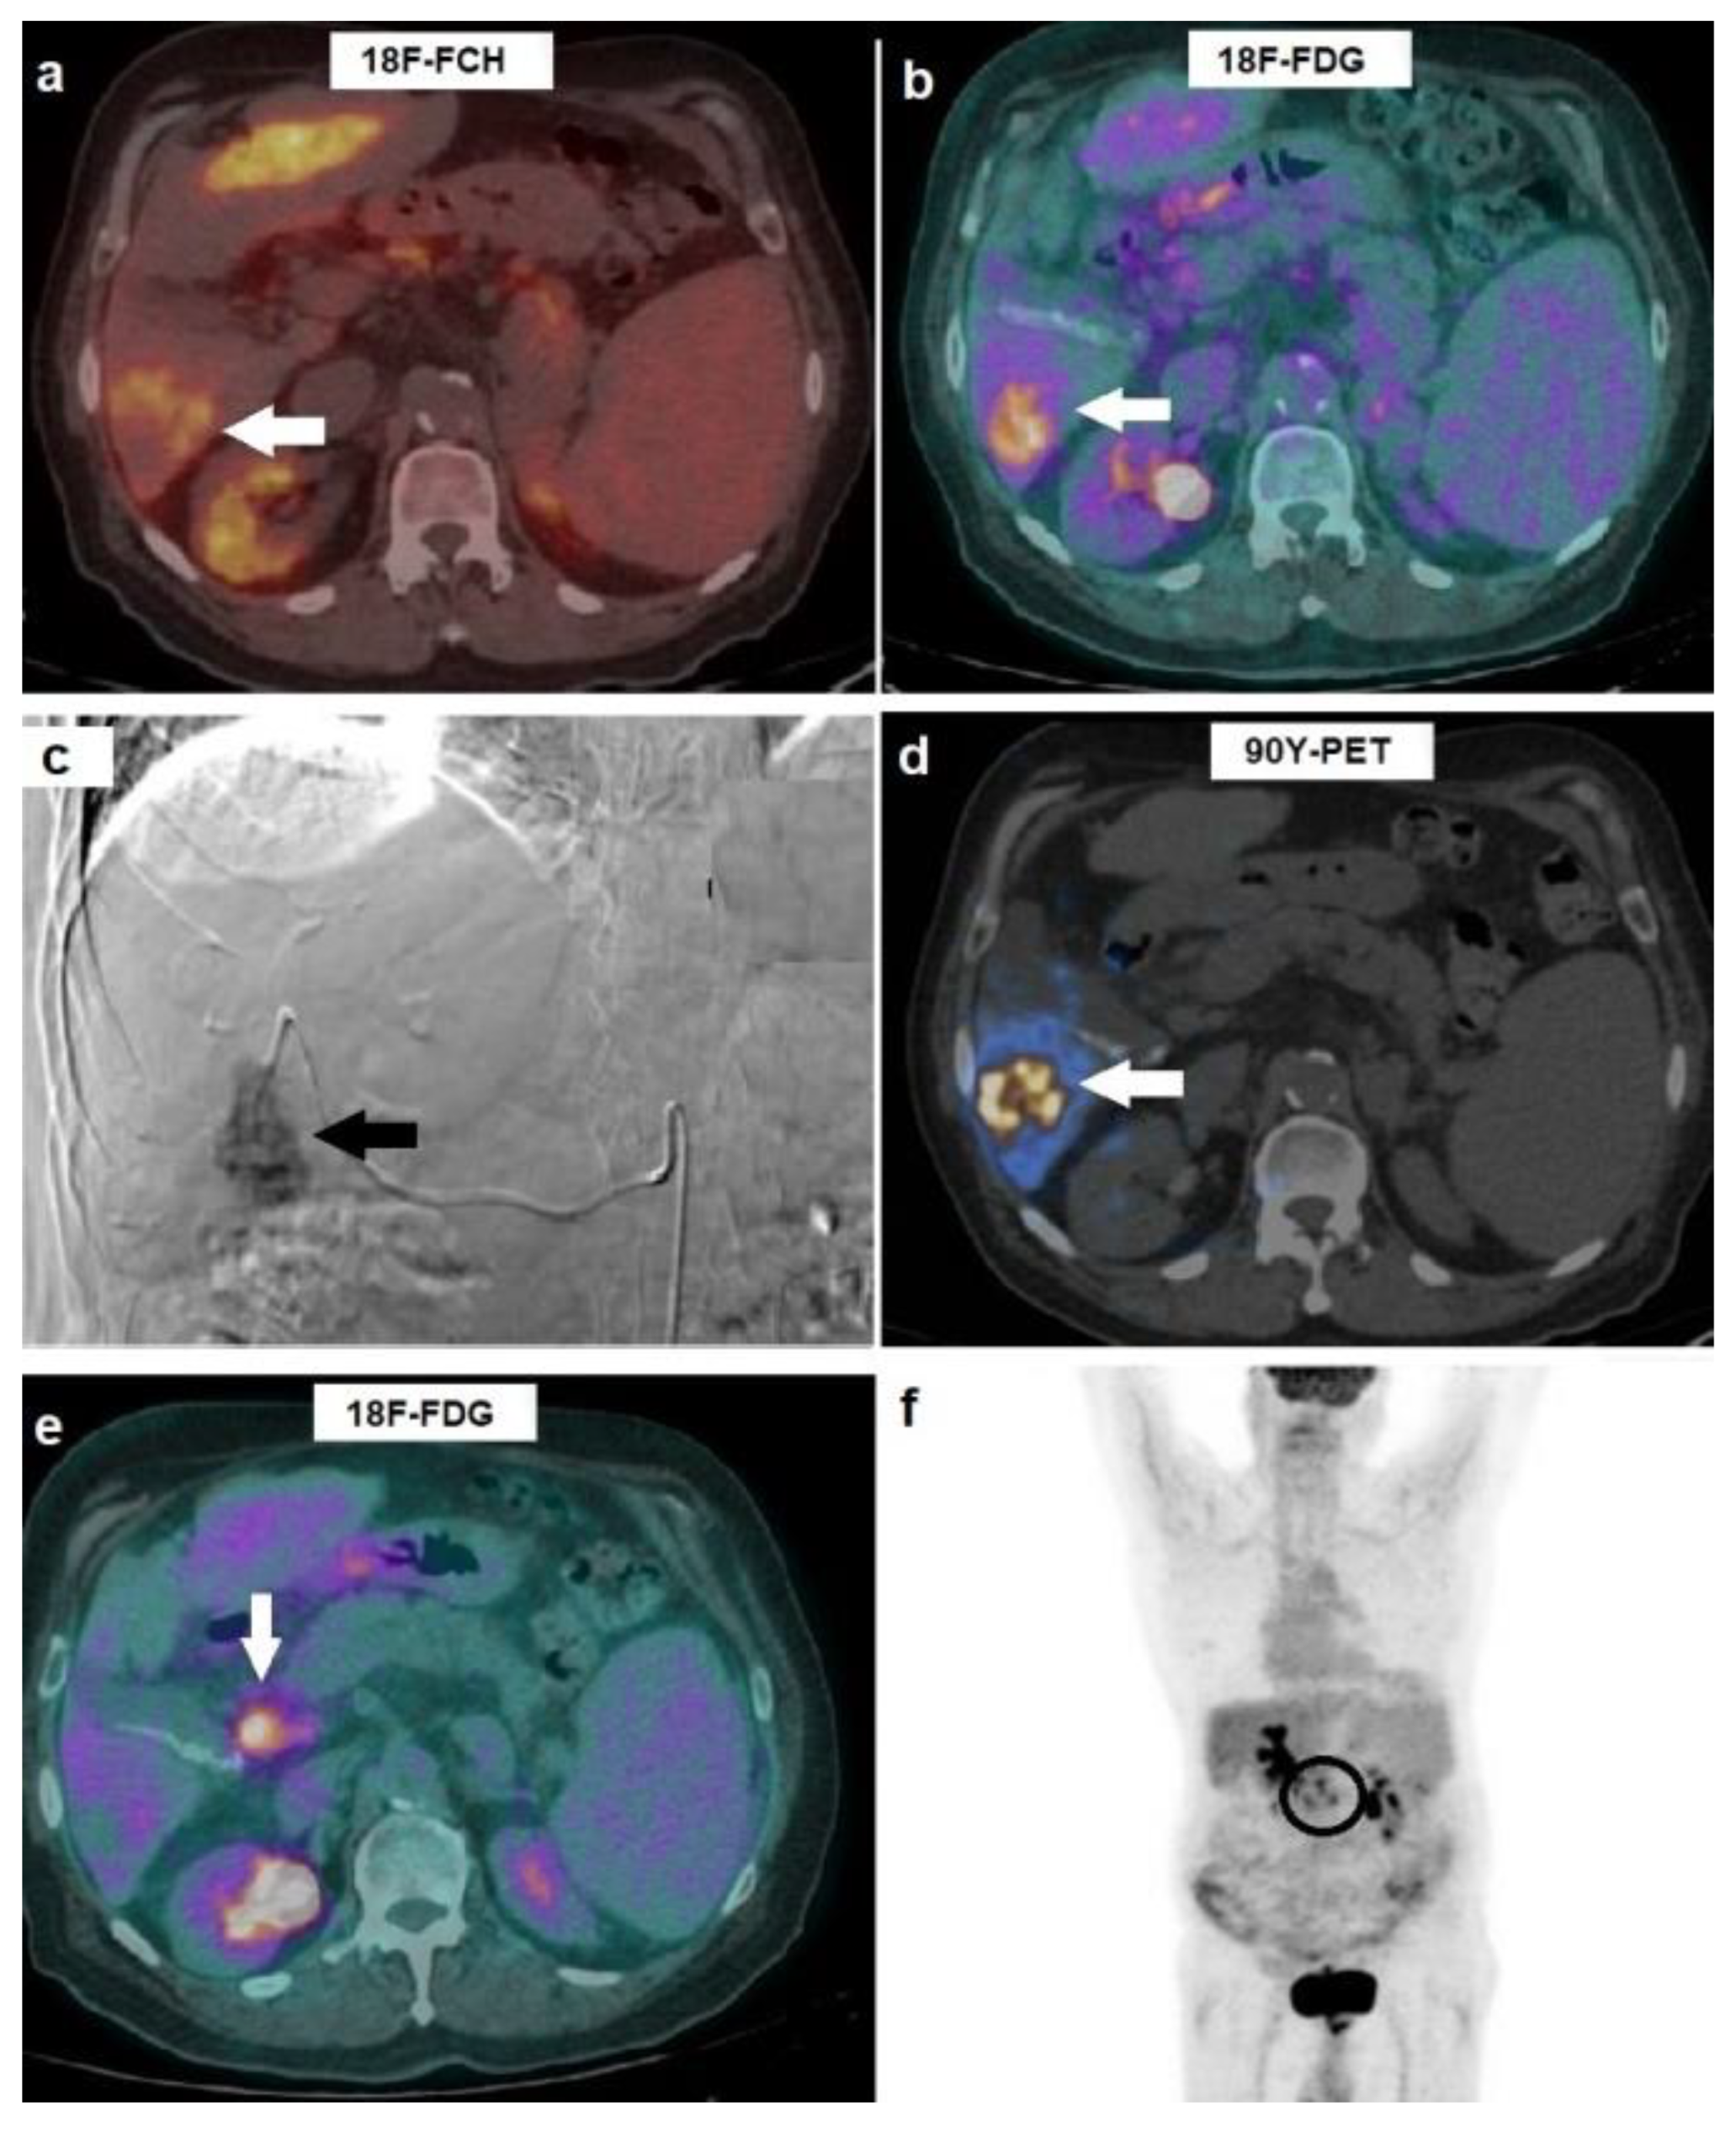

Figure 4. A 51-year-old affected by HCV-related cirrhosis and HCC in the left hepatic lobe, with portal vein invasion, progressive during systemic therapy with sorafenib. On pre-treatment examination, HCC resulted 18F-FCH-negative, but (a) intensely positive on 18F-FDG PET/CT (arrow, SUVmax 17.7). (b) After selective catheterization of HCC’s arterial feeder, he was administered with 90Y-microspheres: 90Y-PET showed a peripheral pattern of accumulation with respect to HCC lesion (arrow). At 8-weeks post-treatment 18F-FDG PET/CT, a complete regression of HCC in the left lobe was evident (c), although the onset of an intensely hypermetabolic celiac lymph adenopathy was detected ((d), arrow). Therapeutic decision was stereotactic RT on the 18F-FDG-positive metastasis. On follow-up 18F-FDG PET/CT carried out at 2 months after RT, complete metabolic response was registered both in the hepatic lesion (e) and in nodal metastasis (f). Overall survival resulted in 36 months.

PET/CT meaningfully affected two out of three patients with evidence of extrahepatic progression on post-treatment 18F-FDG PET/CT. In such cases, stereotactic RT was carried out on metastatic localizations to celiac lymph nodes: post-treatment PET/CT images were utilized to draw biological target volume (BTV) that was incorporated into radiation therapy (RT) planning with optimal clinical and imaging response in both cases, as shown in Figure 4.